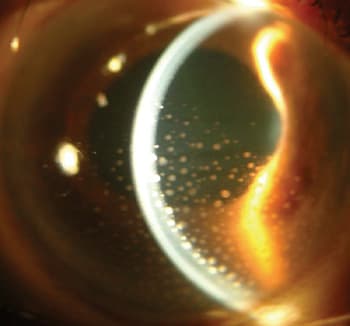

|

Note the many, large keratic precipitates in this uveitis patient. |